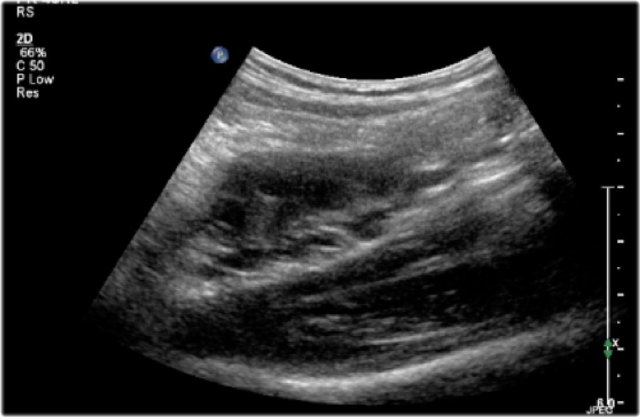

Here an ultrasound image of a five-month-old boy with an antenatally detected dilated pyelocalyceal system and no visible ureter, in accordance with a ureteropelvic junction stenosis.

On a sagittal image the dilated pyelocalyceal system is well seen.